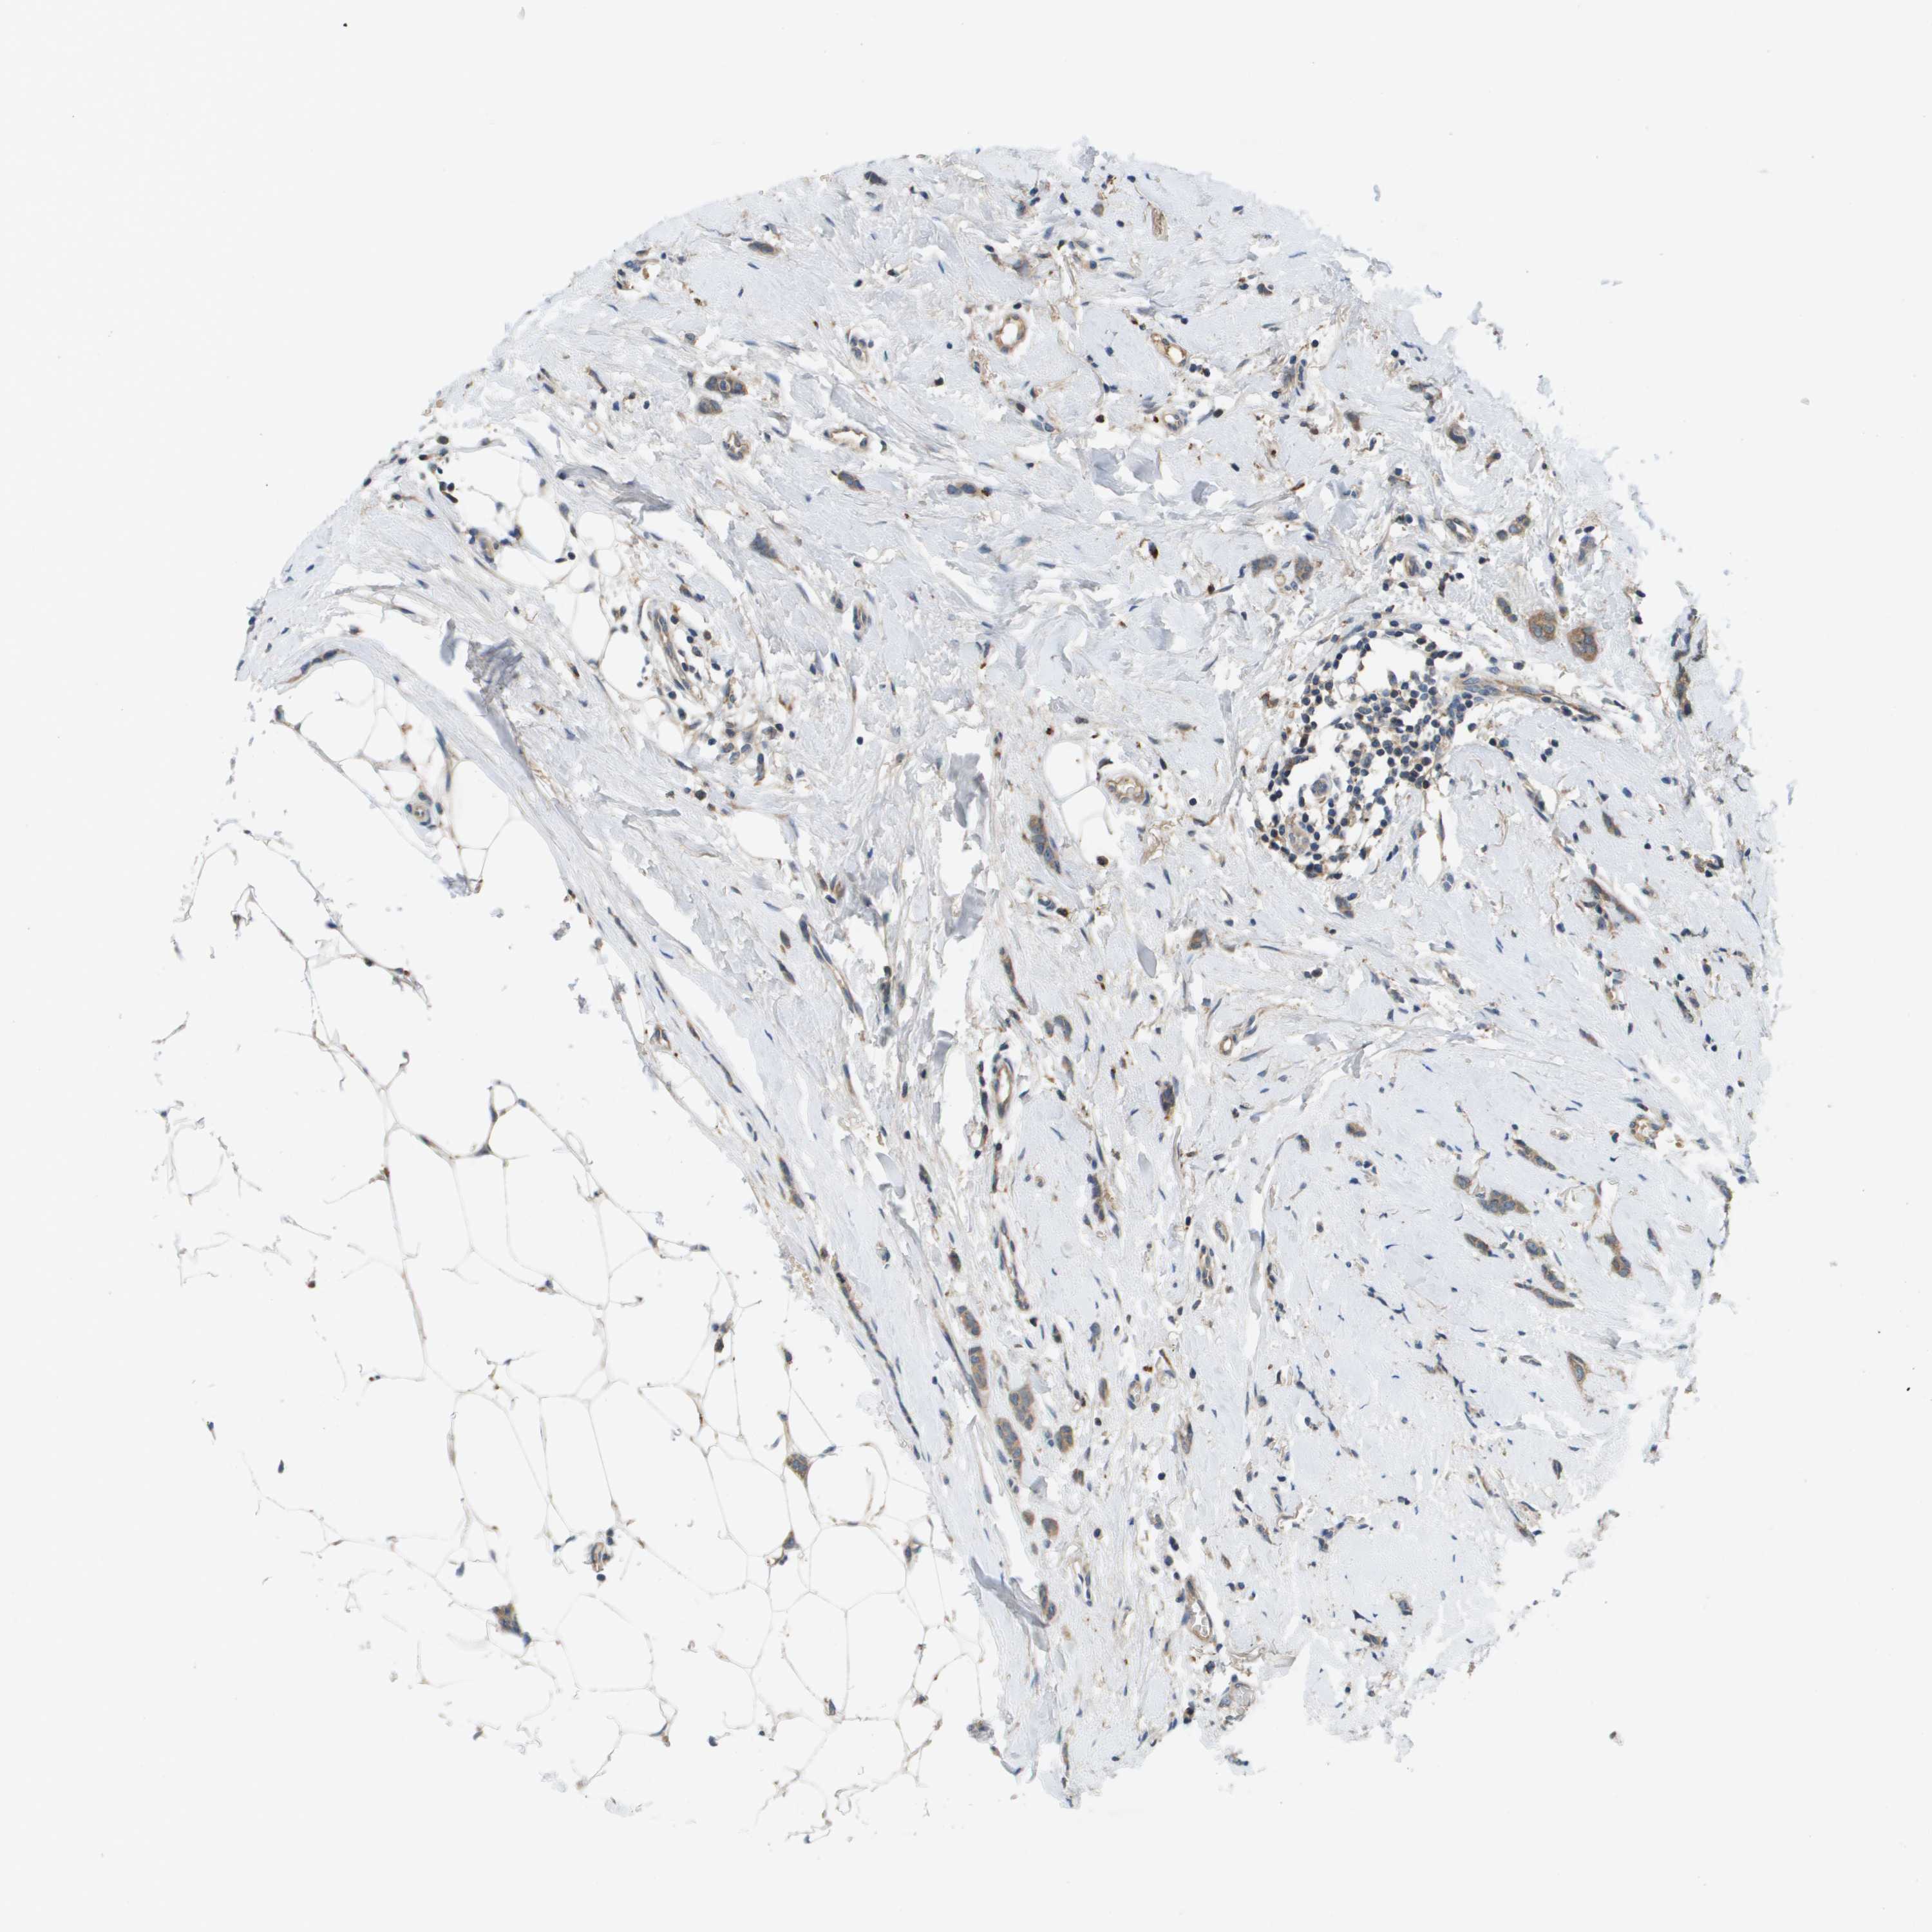

BRCA TCGA BRCA VALIDATION PROTEIN EXPRESSION

ANTIBODIES

AND

VALIDATION